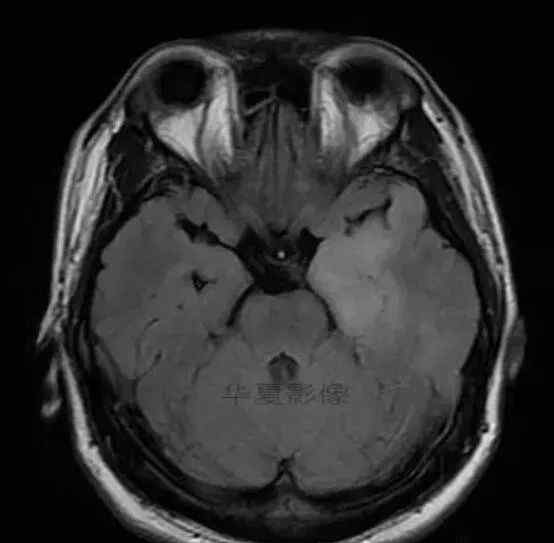

1.左侧颞叶、海马和岛叶T1WI信号低,T2WI信号高

2.病变没有明显的边界

3.占用效果不明显

4.豆状核不受影响